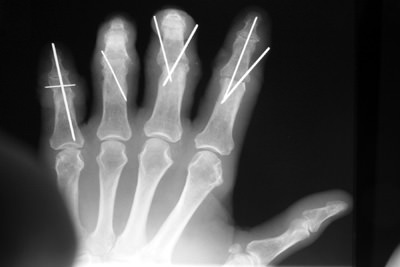

He amputated the four fingers of his left hand and was brought to the local emergency room in a small town on the west coast of Florida. His ER doctor astutely sent his wife back to recover two of the fingers from the workshop floor while he searched the state for a hand surgeon who would accept this challenging case.

Not only was this essentially a four finger amputation, but it occurred in an elderly man with a history of a cardiac stent procedure.

Although it was known to be high risk, JJ felt his life would be over without the use of his hands for woodworking, and insisted upon finding a team who could take on this challenge. Dr. Badia and Dr. Khouri would later successfully reattach all four fingers after the patient was flown by helicopter to Cedars Medical Center.